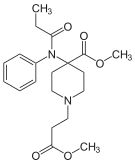

Anilidopiperidines

- 3-Allylfentanyl

- 3-Methylfentanyl

- 3-Methylthiofentanyl

- 4-Phenylfentanyl

- Alfentanil

- α-Methylacetylfentanyl

- α-Methylfentanyl

- α-Methylthiofentanyl

- Benzylfentanyl

- β-hydroxyfentanyl

- β-hydroxythiofentanyl

- β-Methylfentanyl

- Brifentanil

- Butyrfentanyl

- Carfentanil

- Fentanyl

- Lofentanil

- N-Methylcarfentanil

- Mirfentanil

- Ocfentanil

- Ohmefentanyl

- Parafluorofentanyl

- Phenaridine

- R-30490

- Remifentanil

- Sufentanil

- Thenylfentanyl

- Thiofentanyl

- Trefentanil

Structures